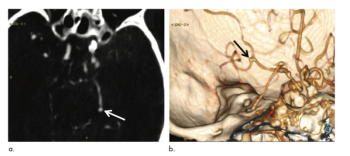

Deep learning tool improves cerebral aneurysm detection, specifically among radiologists with fewer years’ experience.